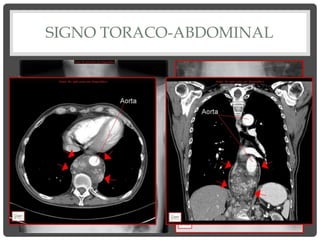

SIGNO TORACO-ABDOMINAL

• Masa que tiene borde

inferior neto, que se

ve a través de

diafragma, es

INTRATORÁCICA.

• Masa que se

ensancha hacia

abajo, sin borde

inferior definido, es

torácica y abdominal.